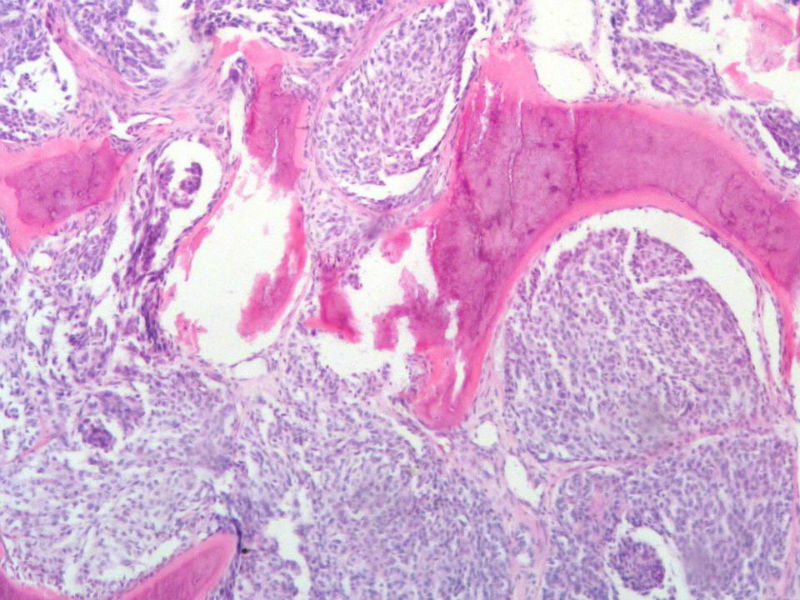

女,64岁,头晕半月,CT检查颅内左颞叶占位,侵犯颅骨和颞肌,手术切除肿物。肉眼,灰白色结节状肿物,3X3X2厘米,边界不清,切面灰黄色,质软。

特别提示:手术前曾做过介入肿瘤栓塞。镜下核分裂15/HP。脑左颞部占位图1

梭形细胞与上皮样漩涡状结构,富于细胞,见个别沙砾体,并见肿瘤性坏死。颅骨及其横纹肌等软组织内见肿瘤呈侵袭性生长。但细胞异型性不是很大。鉴别:

1)恶性脑膜瘤

2)非典型性脑膜瘤

由于非典型性脑膜瘤也可以发生地图状坏死,甚至侵袭性生长。需要计数核分裂数/10HPF,以资鉴别诊断。